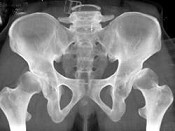

男,23岁,跛行,外展受限,两下肢不等长,结合图像,最可能的诊断是()

• A.髋关节中心脱位

• B.髋关节后脱位

• C.髋关节前脱位

• D.先天性髋内翻

• E.髋关节结核